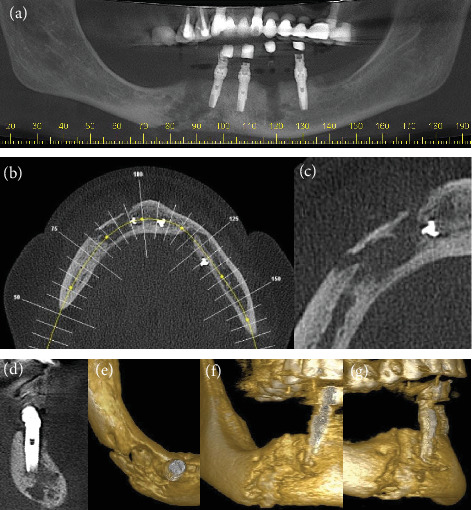

Osteomyelitis is an infection caused by bacterial contamination of the bone marrow, cortical surfaces, and the periosteum. The clinical examination of a patient with severe osteomyelitis secondary to dental implants revealed a large facial swelling, suppuration in the perimandibular region, limited mouth opening, and diffuse pain that started after the placement of five dental implants. Two failed implants were removed, a reconstructive titanium plate was placed, and the patient was treated with antibiotics, but the infection did not resolve. The patient's clinical condition became worse, and she sought hospital care. At presentation, she had a fever and was dehydrated. She was hospitalized for 16 days. Her treatment included surgery for the removal of the reconstructive plate, the implants with peri-implantitis, and bone and necrotic tissue, together with administration of systemic drugs. The diagnosis of osteomyelitis was based on clinical, imaging, and histopathological findings, and she was treated with administration of antibiotics (penicillin, amikacin) for 16 days, followed by cephalosporin for 15 days after hospital discharge. Sixteen days later, her clinical condition was normal. Twelve months later, she received new implants and underwent prosthetic rehabilitation. Imaging tests, surgical elimination of bone and necrotic tissue, and histopathological analyses are essential for an accurate diagnosis. In our case, infection control demanded a careful surgical intervention associated with the administration of systemic antibiotics.